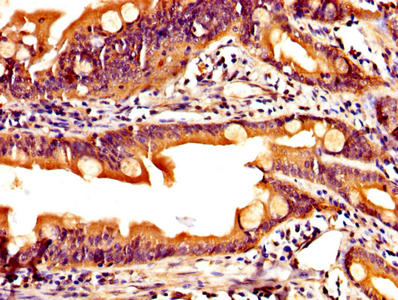

IHC image of CSB-PA12214A0Rb diluted at 1:200 and staining in paraffin-embedded human small intestine tissue performed on a Leica BondTM system. After dewaxing and hydration, antigen retrieval was mediated by high pressure in a citrate buffer (pH 6.0). Section was blocked with 10% normal goat serum 30min at RT. Then primary antibody (1% BSA) was incubated at 4°C overnight. The primary is detected by a biotinylated secondary antibody and visualized using an HRP conjugated SP system.

IHC image of CSB-PA12214A0Rb diluted at 1:200 and staining in paraffin-embedded human colon cancer performed on a Leica BondTM system. After dewaxing and hydration, antigen retrieval was mediated by high pressure in a citrate buffer (pH 6.0). Section was blocked with 10% normal goat serum 30min at RT. Then primary antibody (1% BSA) was incubated at 4°C overnight. The primary is detected by a biotinylated secondary antibody and visualized using an HRP conjugated SP system.